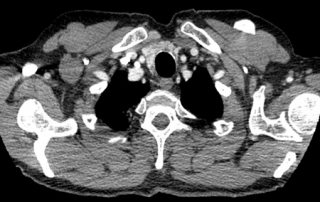

Scanner thorax abdomen pelvien : masse médiastinale antérieure et supérieure, absence d’atteinte du pédicule vasculaire, absence de nodule pulmonaire, scanner sous-diaphragmatique normal. Cible médiastinale taille 94 x 67 mm